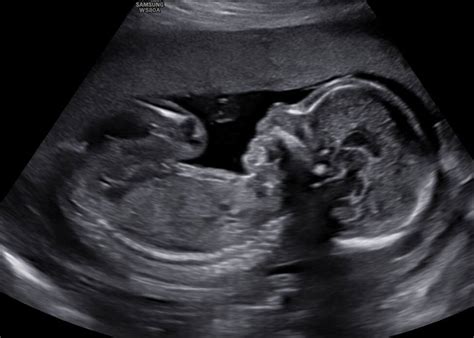

De 20-wekenecho: Een gedetailleerde controle

Rond de 20 weken wordt de structurele echo, ook wel de 20-wekenecho genoemd, uitgevoerd. Tijdens deze echo controleert de gynaecoloog of je baby goed groeit, of er voldoende vruchtwater aanwezig is en of de placenta er goed uitziet.